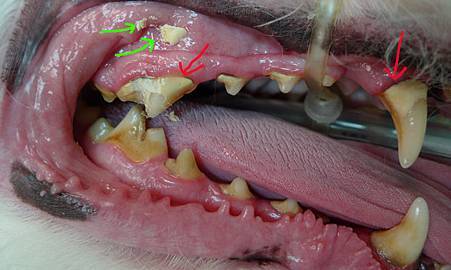

咦? 為什麼跟左邊比 右邊牙齒明顯的就有比較多結石!? (綠箭頭: 撬下來的結石片)

仔細想... 我都是這樣坐著面對面幫ALPHA刷牙

我是用右手的 每次都是先刷她的左半邊牙(比較順手)

左邊好了才會刷右邊 方向上比較不順手 刷久了他也比較會沒耐心的要溜走跑掉

如果兩年來右邊都刷的比左邊潦草 就造成兩側結石情況明顯的差異了!

洗牙完又有亮白的牙齒啦! 今天起兩邊都要好好刷才行!!!!!!!!!!!